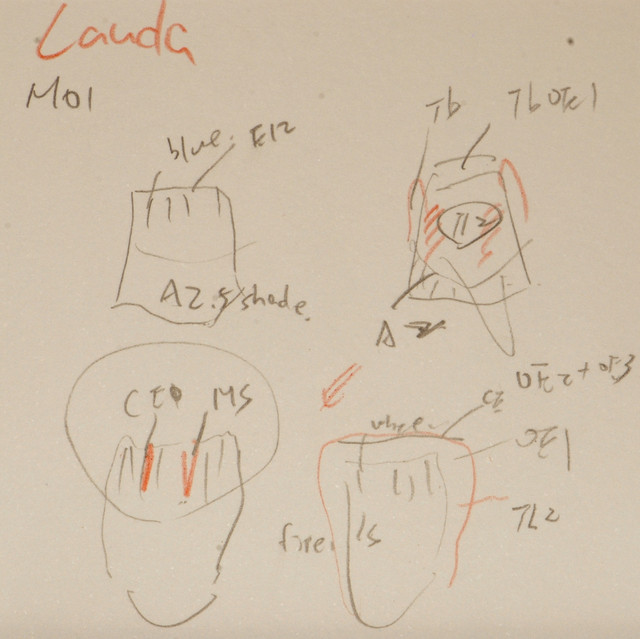

This is a case with mulit-layered e.max crown using MO1 press ingot.

This is a case with mulit-layered e.max crown using MO1 press ingot.Patient mention the colour is too orange , she want more whiter and clear esthetic result, the target shade is between A1 and A2.

What will u gonna to finish this case? I think: it's not only matching the shade guide but also to create a life-like tooth colour structure to reach a harmony esthetical result.

As this black light photo you can see the different layer of porcelain build-up.